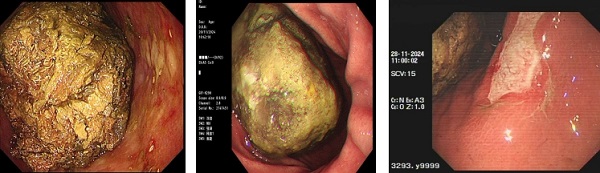

“胃里也会长结石?胃结石是吃出来的?”在消化内科,时常会有患者因空腹进食了柿子、山楂或黑枣等出现腹痛、腹胀、恶心等不适症状,经过检查证实是胃内形成了结石,部分患者甚至因结石排入肠道而导致成肠梗阻。今天就让我们认识一下胃石症。

胃结石是胃内食物被消化后形成的团块状的结构,根据其主要成分可分为植物性胃石、动物性胃石、药物性胃石和混合性胃石四类,临床上以植物性胃石更为常见。

玉溪市人民医院消化内科开展胃结石的治疗,患者可先行口服可乐或碳酸氢钠片,造成胃内低酸环境,有利于胃酸裂解,再配合内镜下机械碎石,达到一次性治愈的疗效。内镜下治疗胃结石具有安全、有效、直观的优势,它利用胃镜设备直接观察胃内结石的情况,并根据结石的大小、形状和硬度选择合适的器械进行碎石操作,经过切碎的小块结石可通过胃肠蠕动顺利排出体外。